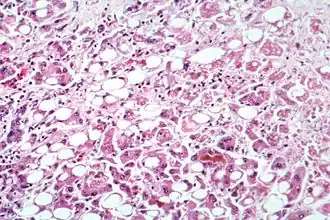

Patogenia

En circunstancias normales, no hay constancia de que ninguno de los virus de la hepatitis sea directamente citopático para los hepatocitos. Los datos disponibles sugieren que las manifestaciones clínicas y la evolución que siguen a la lesión hepática aguda propia de una hepatitis vírica son determinadas por las respuestas inmunitarias del paciente.